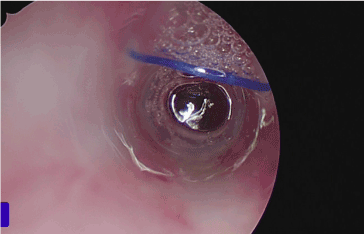

During this procedure, we perform direct laryngoscopy and using a 0-degree Hopkins rod telescope (Karl Storz, USA, El Segundo, CA) we visualize the endolumen of the stent and under bronchoscopic visualization, we cut the stent stitch with a laryngeal scissors (Figure 3). We then secure the stent using an endoscopic alligator clamp. The portion of the stitch emanating from the right side of the skin incision is grasped and removed percutaneously. The stent then can be removed transorally with the alligator clamp.

Figure 3: Cutting the endoluminal suture with endoscopic scissor.